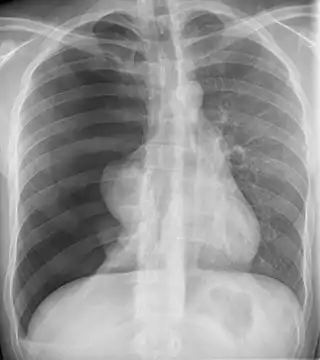

![]() Radiografía de un neumotórax. La amplia mayoría de los neumotórax catameniales ocurren en el lado derecho, al igual que en este caso. | ||